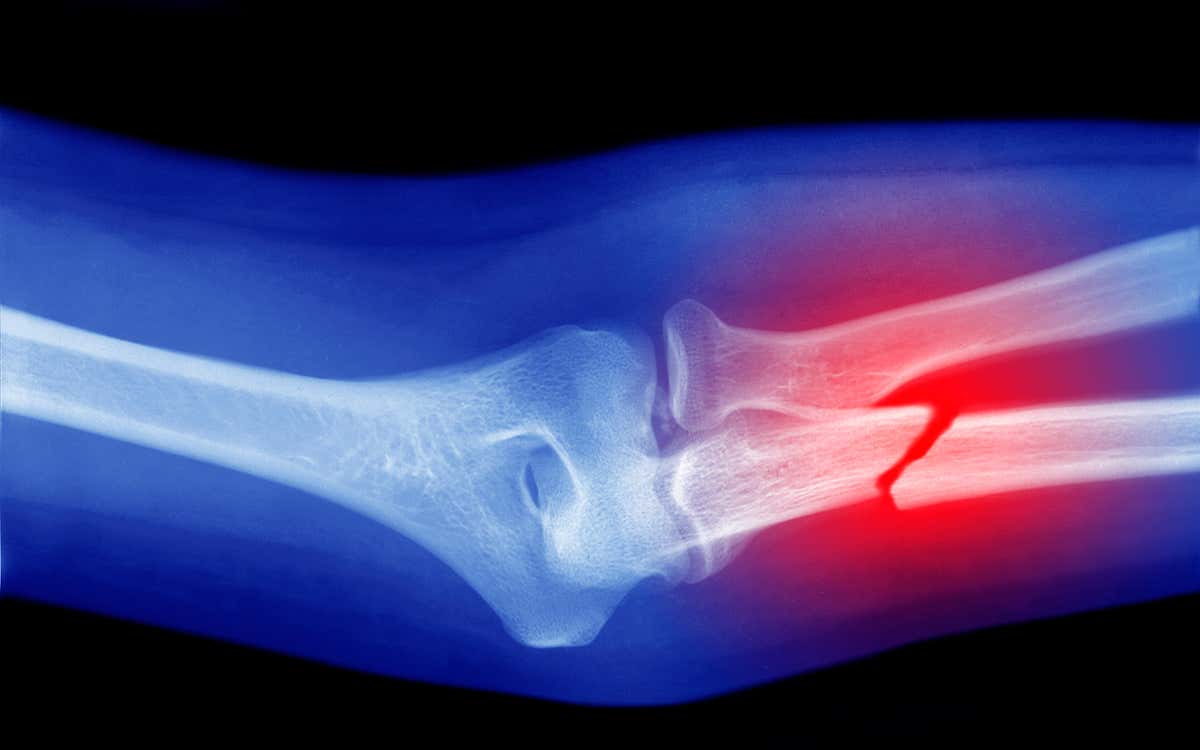

The affected family members include a 78-year-old woman, her two middle-aged daughters, and their three children. All of them fail to sense pain in the way most of us do, and don’t notice when they are being injured. When they were assessed, the family members were found to have bone fractures in their arms and legs that they hadn’t realised were there.

“Sometimes they feel pain in the initial break but it goes away very quickly,” says James Cox, of University College London. “For example, Letizia broke her shoulder while skiing, but then kept skiing for the rest of the day and drove home. She didn’t get it checked out until the next day.”